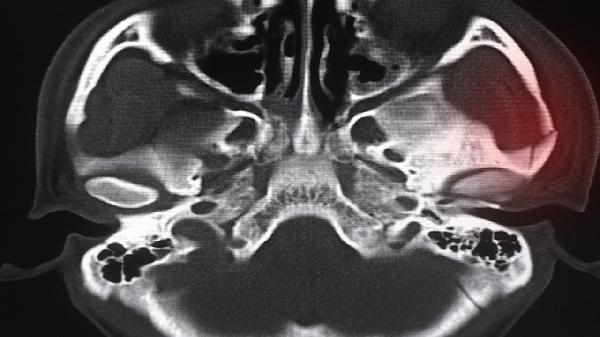

日常应注意保持正确坐姿,避免长时间低头使用电子设备,每小时进行颈部伸展运动。睡眠时选择高度适中的枕头,可进行游泳、羽毛球等有利于颈椎健康的运动。饮食中适当增加富含钙质的乳制品、豆制品,补充维生素D促进钙吸收。出现持续疼痛、肢体麻木或活动受限时应及时就医,通过X光、CT或核磁共振明确诊断。